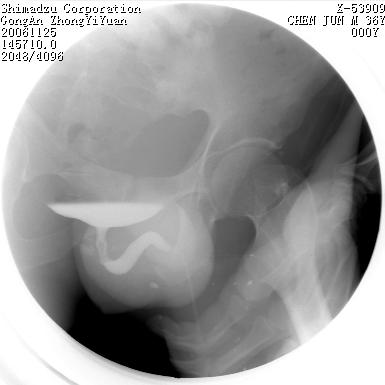

男 66岁 排尿困难半年;此人腹腔及腹膜后积液.

尿道充盈缺损,考虑占位.

后尿道内充盈缺损;前列腺结石。

后尿道狭窄,其中可见充盈缺损,我认为应先排除结核.

后尿路精阜水平充盈缺损,考虑结石或占位病变可能,建议mri检查,精阜水平尿路周围条索状密度增高影,考虑造影剂逆流入输精管或周围静脉。